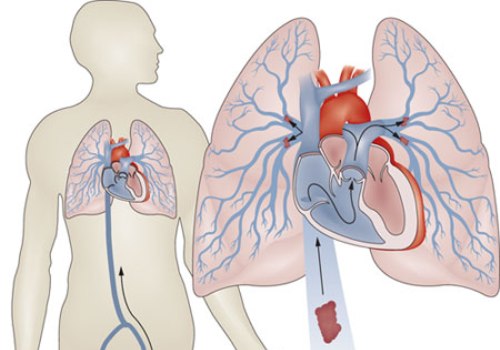

Чаще всего кислородное голодание легкого наступает из-за тромбоза (образования кровяного сгустка на внутренней стенке артерии, закупоривающего ее просвет) или эмболии (закупорки инородным телом, принесенным с током крови из любого участка человеческого тела – в данном случае оно называется эмболом). Реже патологический процесс наступает из-за сдавливания кровеносного сосуда извне. Инфаркт легкого также называют легочной эмболией, подразумевая под эмболией закупорку сосуда в общем, независимо от закупоривающего фактора.

- тромбозы вен (чаще – глубоких) нижних конечностей;

Особенно опасны тромбы, которые к внутренней поверхности сосуда крепятся очень маленькой поверхностью (в сравнении со всей площадью своей поверхности). Такие тромбы называются флотирующими (плавающими). Они практически всегда отрываются и заносятся током крови в долевые и сегментарные сосуды легкого.

Классически инфаркт легкого может развиться от 2-3 часов до суток. После острого периода в пострадавшие ткани откладываются солевые соединения – процесс называется организацией. Длится он не более 7 суток.